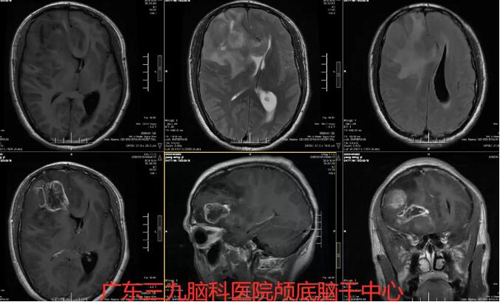

图2:术前MR右侧额叶示团片状不均匀长T1长T2信号,FLAIR序列呈稍高信号,增强扫描其内示多发花环状及结节状强化,其范围约为49×43×49mm,周围示大片稍长T1长T2信号,FLAIR序列高信号水肿影,累及胼胝体膝部、右侧基底节、右侧颞叶。右侧侧脑室及左侧侧脑室前角受压并向左侧移位,左侧侧脑室后角稍扩张,周围示少许斑片状FLAIR序列高信号。

图3:术前术后MR示术后改变。